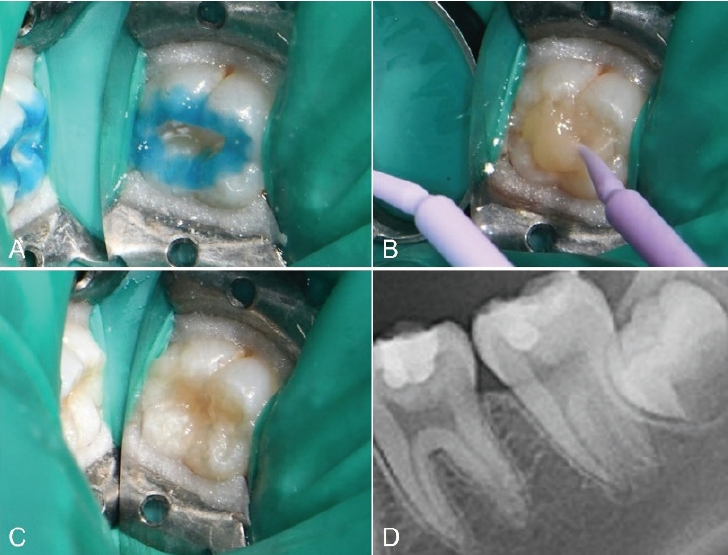

14세 남성 환자가 부산대학교치과병원 치과보존과에 좌측 하악 구치부 우식을 주소로 내원하였다. 환자의 전신 병력 및 치과 병력 특이사항은 없었다. 구내 검사에서는 좌측 하악 제2대구치에서 치면열구 우식이 관찰되었다. 교합면 형태는 보존되어 있었고, 명확한 공동(cavitation)은 관찰되지 않았다(Fig. 1A). 냉자극과 온자극에 대한 반응은 정상적이었다. 타진이나 저작에 대한 통증도 없었다. 파노라마 및 구내치근단방사선 상 상아질까지 진행된 깊은 우식을 관찰할 수 있었다(Figs. 1B and C). 이 결과를 바탕으로 우식 부위를 복합레진으로 수복하면서 스탬프 테크닉을 적용하기로 결정하였다.

Fig. 1.

Initial examination radiograph and clinical photograph. A. No loss of tooth structure is observed. B. Pre-operative radiograph. C. Caries of dentin is seen on olwer left second molar.